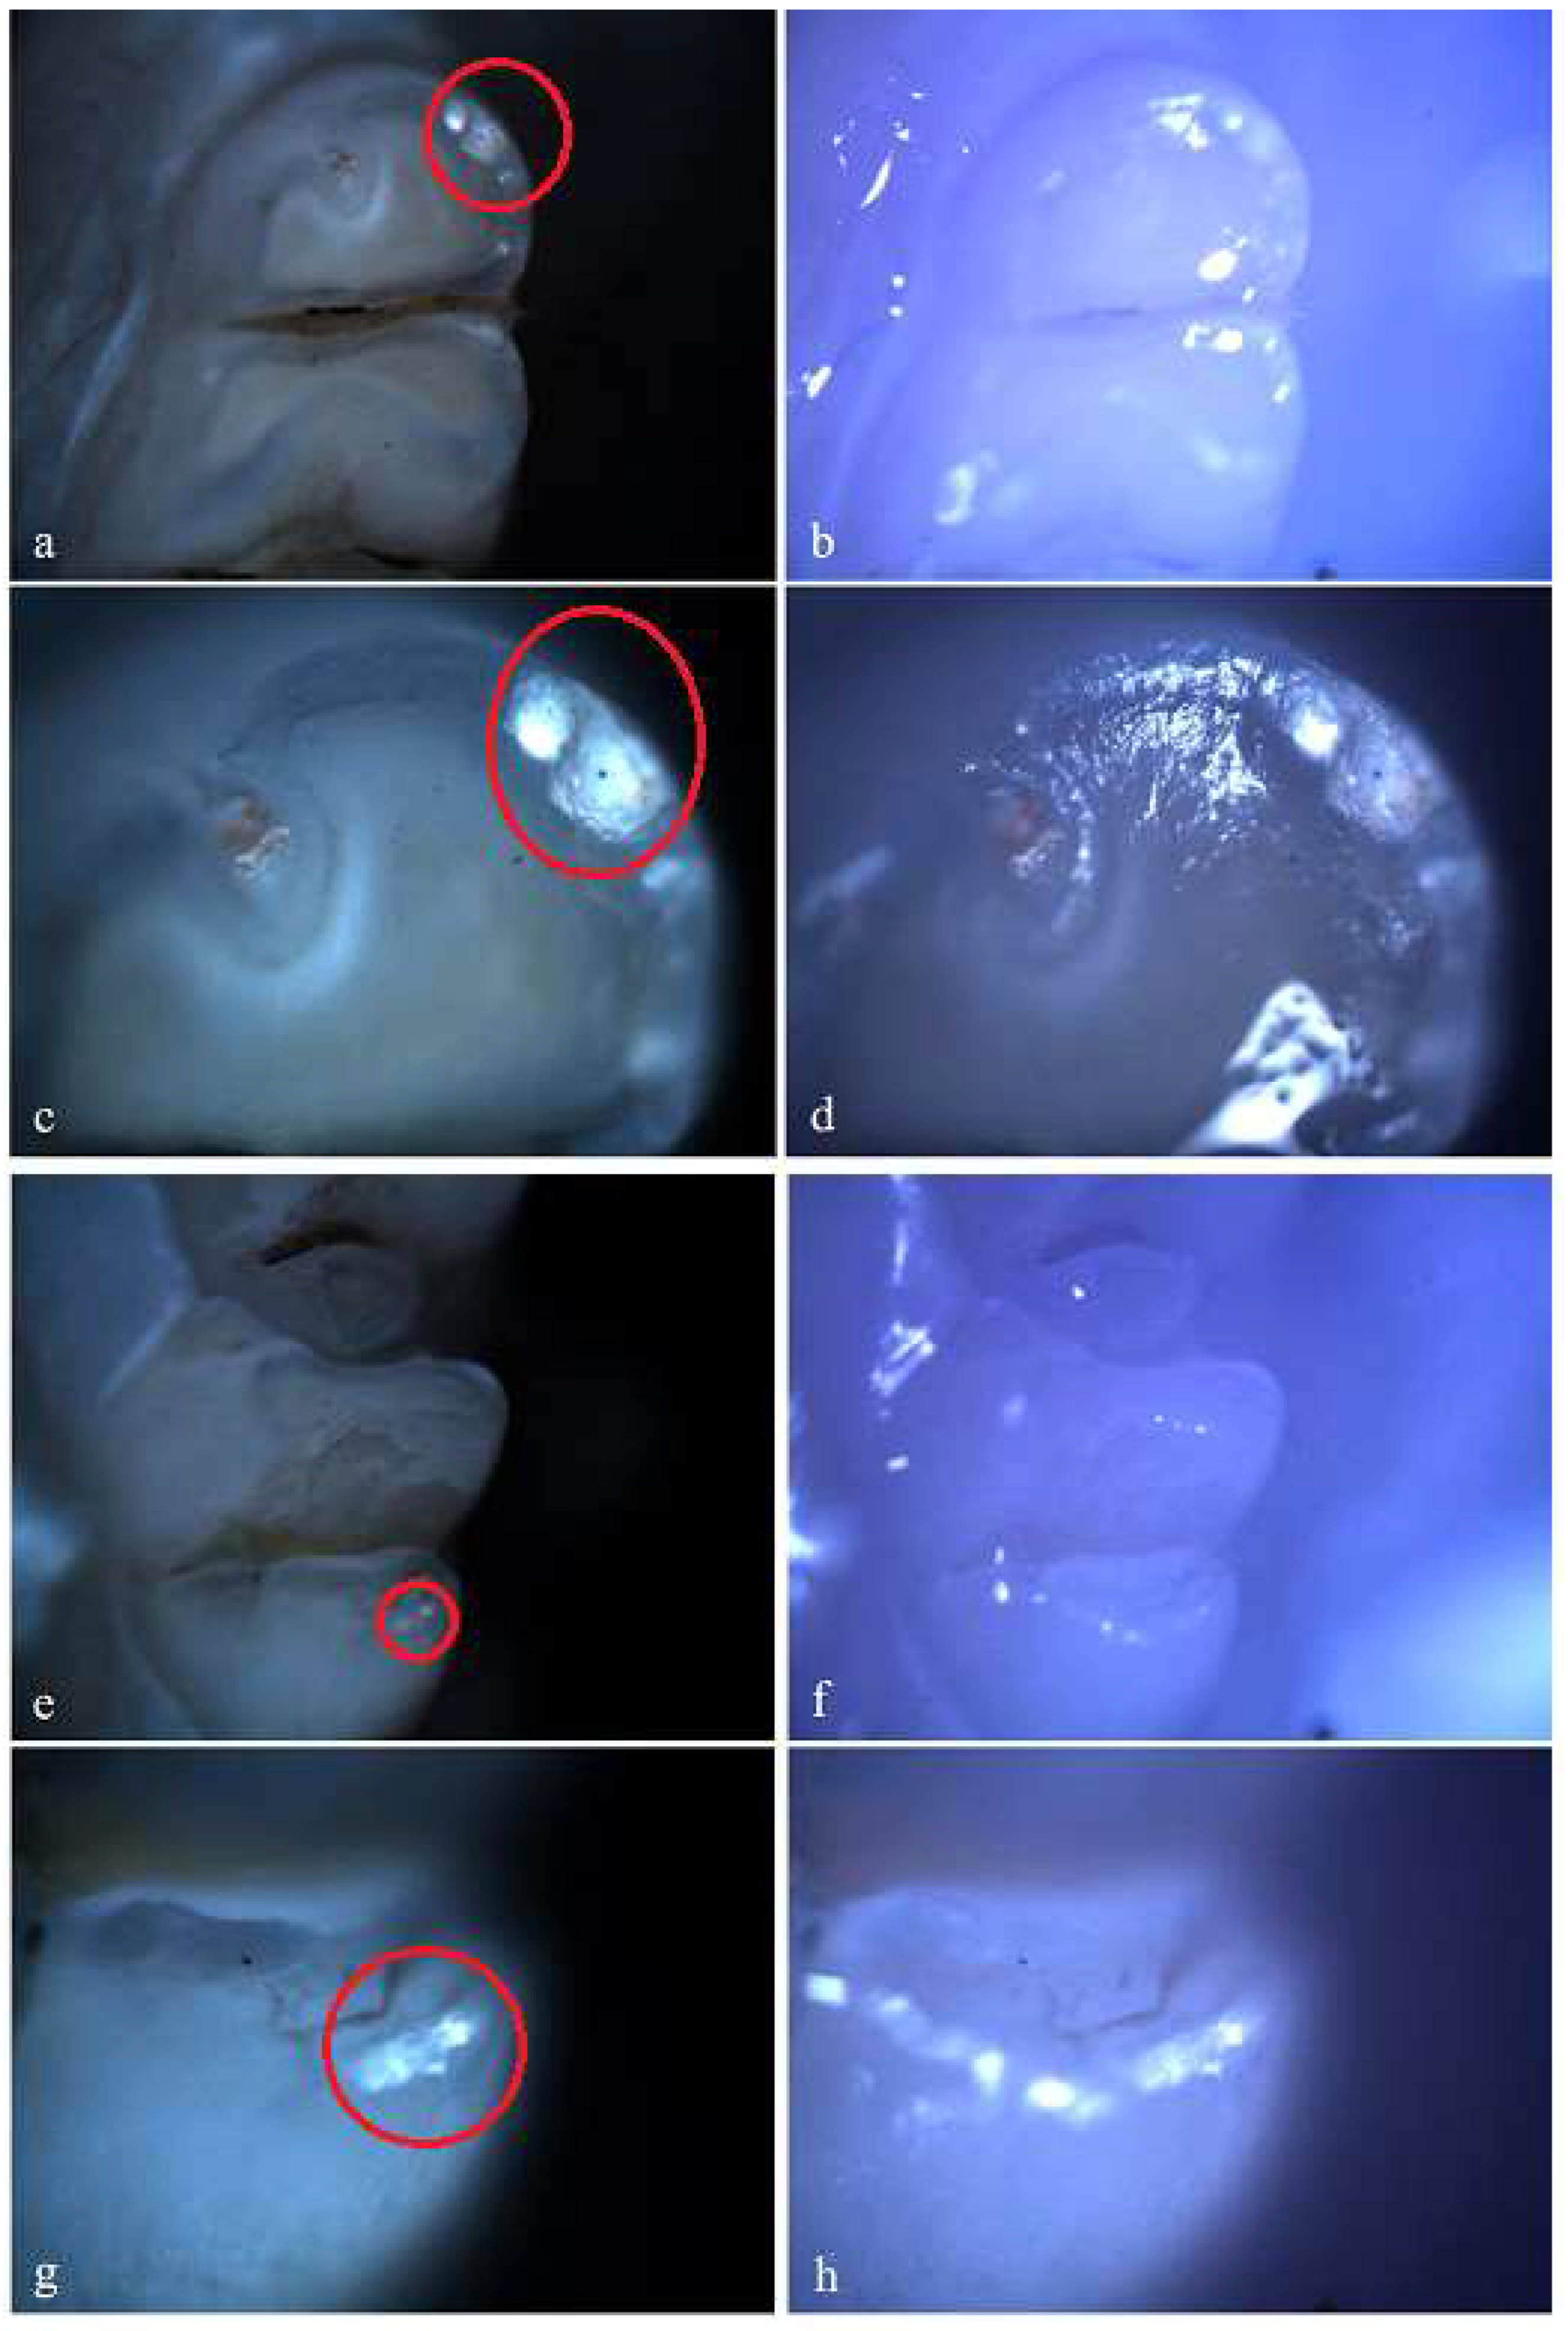

Figure 7. Hypoplasia on the palatal surface of a molar (a - Polarized microscopy image, 4X objective; b - Optical microscopy image, 4X objective) and on the distal surface of a molar (c - Polarized microscopy image, 4X objective; d - Optical microscopy image, 4X objective); Demineralization on the occlusal surface of 2 molars (e, g - Polarized microscopy image, 4X objective; f, h - Optical microscopy image, 4X objective). .

In the group receiving double-dose amoxicillin (100 mg/kg), 13 rats (86.67%) showed at least one clinical form of DDE. Of these, 7 rats were affected by hypoplasia and 5 rats were affected by demineralization. One rat showed both clinical forms of DDE. Within this group, out of a total number of 240 teeth, 43 teeth (17.92%) had at least one lesion. Among them, 13 teeth (30.23%) were incisors and 30 teeth (69.77%) were molars, and as a clinical form of DDE, 25 teeth (58.14%) showed hypoplasia (5 incisors and 20 molars) and 18 teeth (41.86%) showed demineralization (8 incisors and 10 molars). Among the 43 teeth with DDE, 3 teeth showed DDE on 2 surfaces, resulting in 46 affected tooth surfaces.

Figure 8. Hypoplasia on the palatal surface of a molar (a - Polarized microscopy image, 4X objective; b - Optical microscopy image, 4X objective) and on the distal surface of some molars (e, g - Polarized microscopy image, 4X objective; f, h - Optical microscopy image, 4X objective); Demineralization on the occlusal surface of a molar (c - Polarized microscopy image, 4X objective; d - Optical microscopy image, 4X objective) and on the buccal surface of a molar (e - Polarized microscopy image, 4X objective; f - Optical microscopy image, 4X objective).

In the standard dose amoxicillin group (50 mg/kg), 10 rats (66.67%) showed at least one clinical form of DDE. Of these, 6 rats showed hypoplasia and 3 rats showed demineralization. One rat showed both clinical forms of DDE. Within this group, out of a total number of 240 teeth, 25 teeth (10.42%) showed at least one clinical form of DDE. Among them, 8 teeth (32%) were incisors and 17 teeth (68%) were molars, and as a clinical form of DDE, 16 teeth (64%) showed hypoplasia (5 incisors and 11 molars) and 9 teeth (36%) showed demineralization (3 incisors and 6 molars). Among the 25 teeth with DDE, 12 teeth (48%) presented lesions that were located on 2 surfaces, thus resulting in a total of 37 tooth surfaces with DDE.